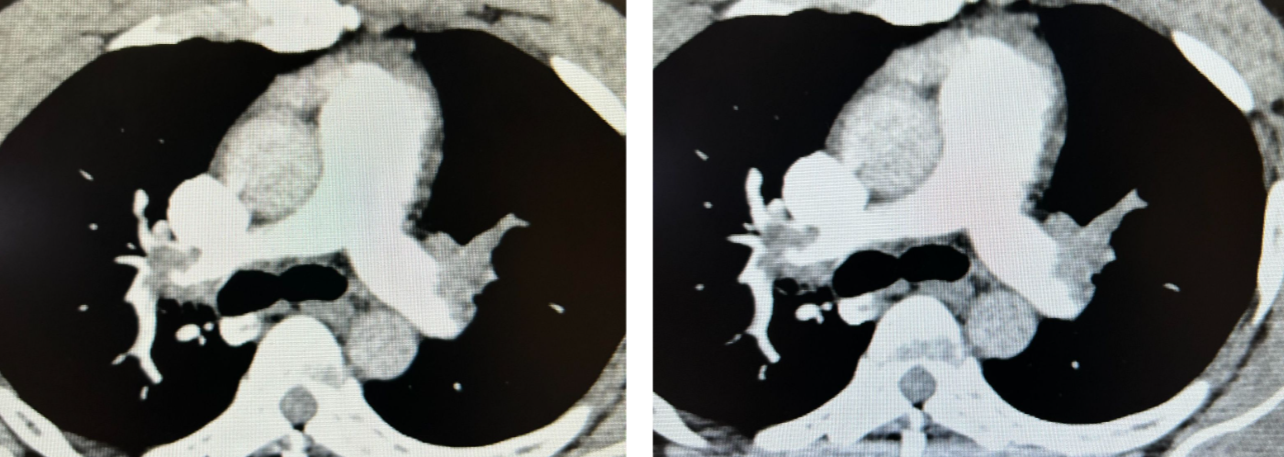

Acute right heart strain was suspected on ECG and bedside echo.

- Acute pulmonary embolism was confirmed on CT angiogram:

- CT angiogram confirmed the diagnosis of acute PE.